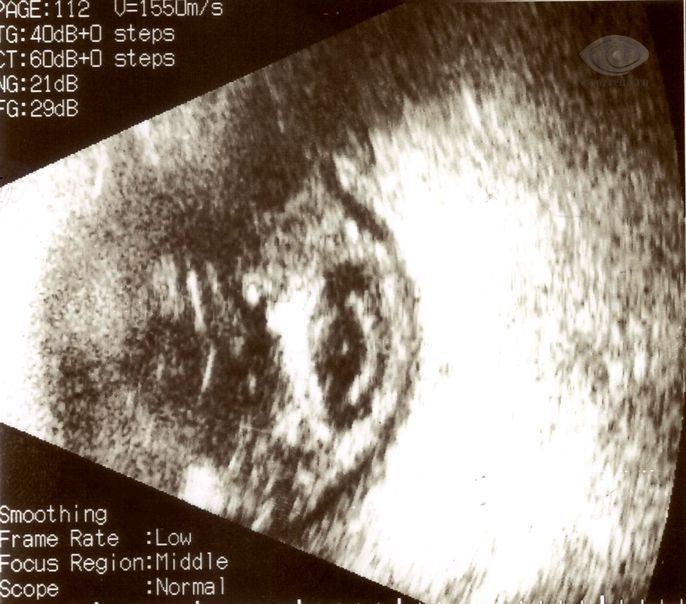

Ультразвуковое исследование глаза позволяет выявить отек оболочек и помутнения в стекловидном теле, что указывает на активный воспалительный процесс.

Симптомы и диагностика: Основные симптомы эндофтальмита включают резкую боль в глазу, снижение зрения, покраснение и отек. Для диагностики заболевания часто используются методы визуализации, такие как УЗИ глаза, а также анализы на наличие инфекционных агентов.

Симптомы эндофтальмита могут включать резкую боль в глазу, покраснение, отек век, ухудшение зрения и наличие гноя. Для диагностики используются клинические осмотры, анализы на наличие инфекционных агентов и визуализирующие методы, такие как УЗИ глаза или компьютерная томография.